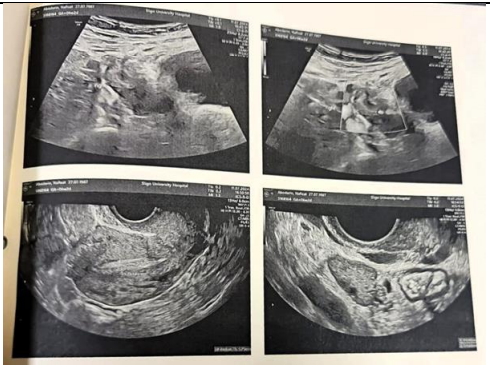

Ultrasound Findings: Uterine lining measuring 5.3 mm, right adnexal mass (8x6x6 mm), and no free fluid. (Fig 1)

Figure 1: USG on first visit 11/07/24